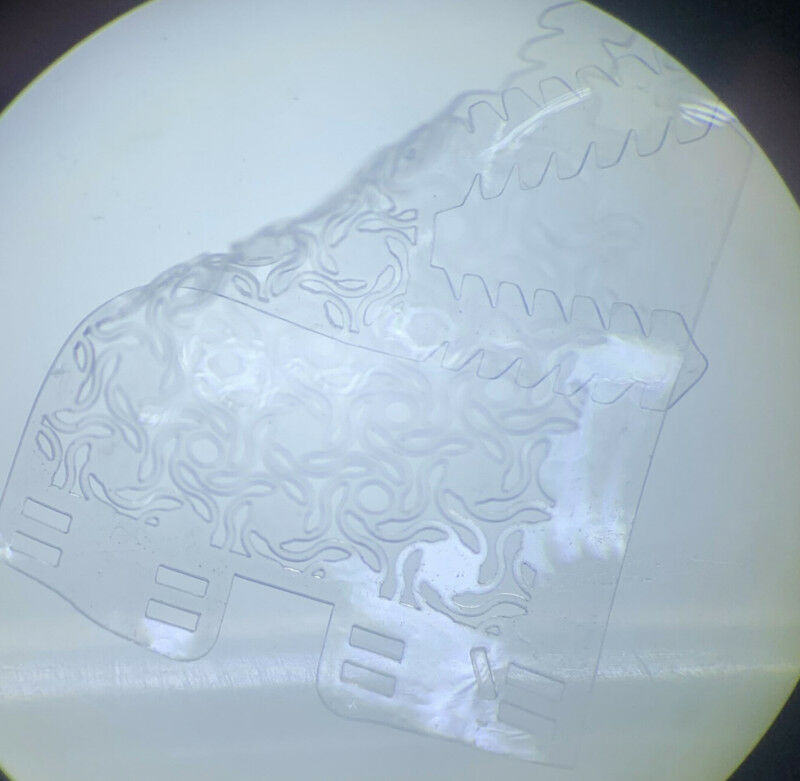

Professor Green’s project will focus on improving the way in which electronic devices interact with the peripheral nervous system, primarily for controlling upper limb prostheses used by amputees.Professor Green explained: "Peripheral nerves carry sensory and motor information between the brain and the rest of the body. Technologies that can monitor and control this flow of information are called peripheral nerve interfaces (PNIs) and they are widely used for neuroprosthetic control, as well as the treatment of multiple neurological and metabolic disorders.

"However, current PNIs are made from materials that are fundamentally different from biological tissues, and this often results in progressive nerve damage and poor device performance."